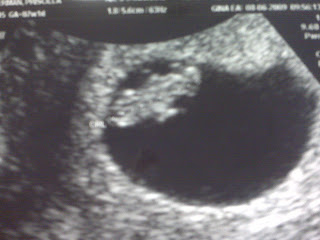

I have been doing a lot more updating on our baby website: www.babyhalterman.com. Feel free to follow that for more pictures, and baby related stuff. The above picture is from our seven-week sonogram, which was purely amazing. The heartbeat was 162, which is a little on the fast side. Some say that could mean it’s a girl, but I think it’s just taking after his/her momma–already high strung!